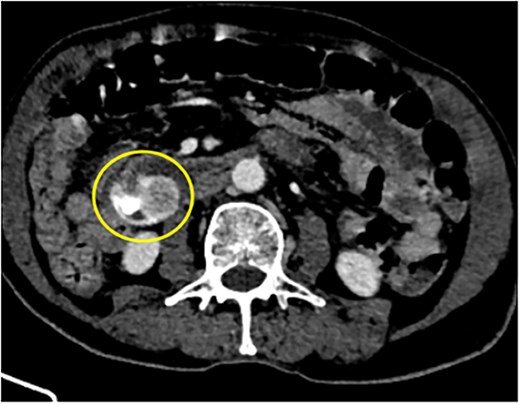

Our case series includes six patients from ages 55–88 years diagnosed with small intestinal GISTs, presenting with varied clinical manifestations between 1 January 2023 and 31 June 2024. The most common presentation was gastrointestinal bleeding in three cases (Figs 1 and 4), followed by one case each of intestinal obstruction (Fig. 3) and perforation (Fig. 5), both of which presented with abdominal pain. One patient was incidentally diagnosed (Fig. 2) during imaging for unrelated symptoms. Tumour locations included the jejunum in three cases, duodenum in two cases, and one in ileum. Tumour sizes ranged from 2 to 15 cm. Surgical interventions included segmental bowel resections with anastomosis for jejunal and ileal tumours, and wedge resections for duodenal lesions. Postoperative recovery was generally uneventful, except for two cases of paralytic ileus, which resolved with conservative management. Histopathology confirmed the diagnosis of GIST with low mitotic index of ≤5 mitoses/mm2, except for one case where wit was >5 mitoses/mm2.

88Y/M with 2 episodes of black tarry stool, axial view of the contrast-enhanced computed tomography (CECT) abdomen showing a heterogenous mass with extravasation of contrast material, signifying the source of hemorrhage.